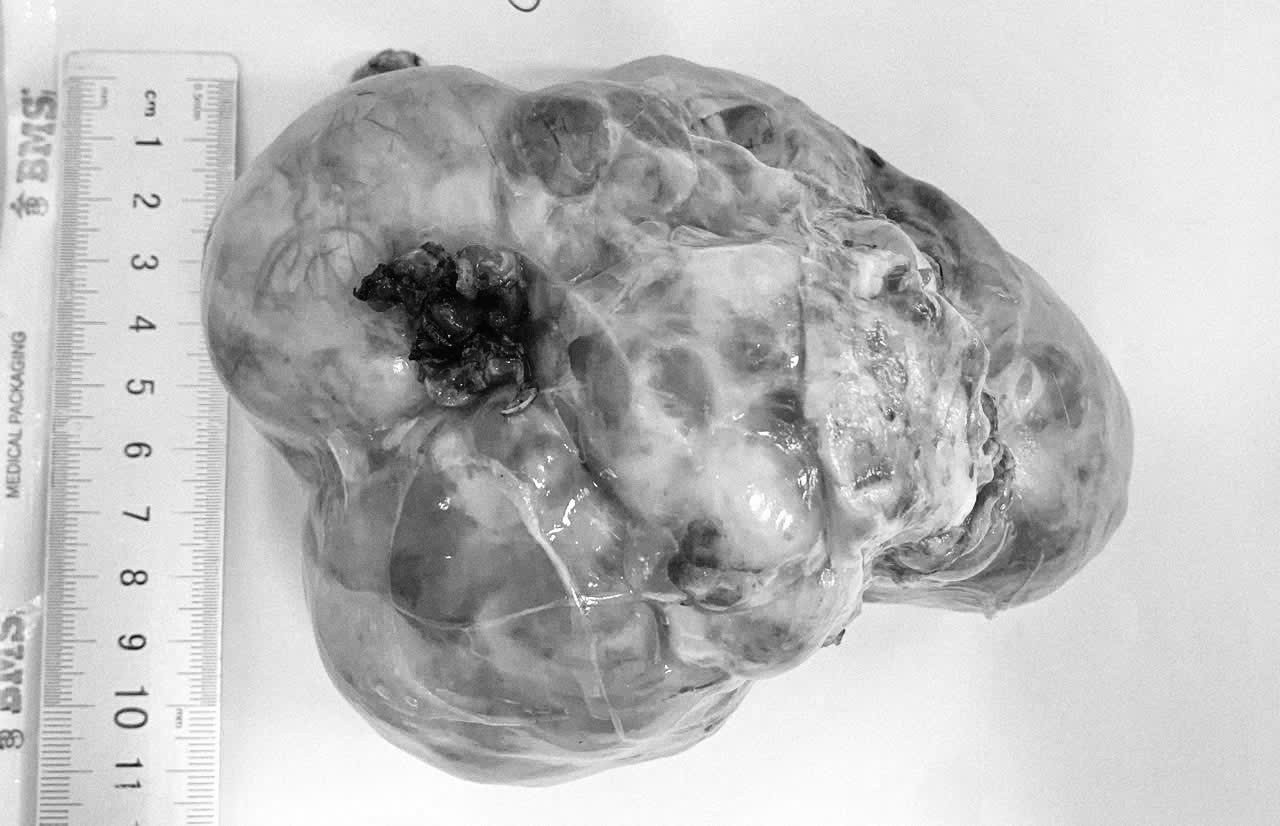

Một khối u được lấy ra từ bệnh nhi. Ảnh: Minh Hiền